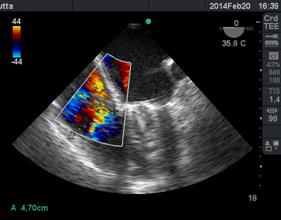

Luego con Doppler Color, analizamos la dirección del chorro regurgitante que es opuesta a la valva comprometida, el tamaño del jet regurgitante y su relación con el área de la aurícula izquierda (AI). Debemos tener en cuenta que el mapeo color del chorro regurgitante está influenciado por parámetros del ecógrafo: ganancia, PRF, límite de Nyquist, y por parámetros fisiológicos: presión arterial, volemia.

Otro factor que afecta el tamaño del chorro es la dirección de éste, los centrales en la aurícula aparecen más grandes con Doppler Color, que aquellos excéntricos que corren sobre la pared auricular, generando un efecto coanda (Figura 15), con un volumen regurgitante muy similar y que por su sola presencia le confiere severidad.

Figura 15 imagen de 4 cámaras medioesofágico con insuficiencia mitral severa, observada con Doppler color (escala 64) con efecto “coanda”, reflujo hacia la pared de AI.

Clasificamos la IM en leve si el área del jet es < 4cm2, o <20% del área de la AI; moderado de 4-8cm2 y severo mayor de 8cm2.